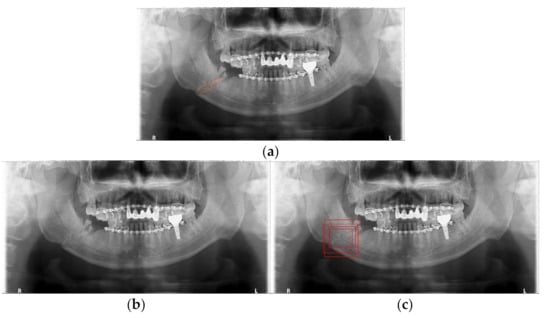

3.2. Detection Results